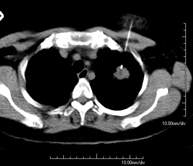

CT-guided thoracic biopsy

It consists of obtaining a tissue sample from a specific thoracic lesion, such as the lung, mediastinum, sternum, etc. It is sometimes performed under sedation with the help of an anaesthesia team. Needles are used to draw a cylinder sample from the lesion to be studied, which is then sent to the Pathology Department for histological analysis. The entire procedure is monitored using images obtained by computed tomography (CT) at various stages of the biopsy, using CT fluoroscopy. After the test, the patient remains in hospital under observation. Coagulation tests must be performed before the puncture.